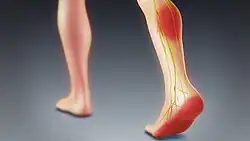

Sciatica is pain going down the leg from the lower back.[1] This pain may extend down the back, outside, or front of the leg.[3] Onset is often sudden following activities such as heavy lifting, though gradual onset may also occur.[5] The pain is often described as shooting.[1] Typically, symptoms occur on only one side of the body;[3] certain causes, however, may result in pain on both sides.[3] Lower back pain is sometimes present.[3] Weakness or numbness may occur in various parts of the affected leg and foot.[3]

Definition

The term "sciatica" usually describes a symptom—pain along the sciatic nerve pathway—rather than a specific condition, illness, or disease.[4] Some use it to mean any pain starting in the lower back and going down the leg.[4] The pain is characteristically described as shooting or shock-like, quickly traveling along the course of the affected nerves.[12] Others use the term as a diagnosis (i.e. an indication of cause and effect) for nerve dysfunction caused by compression of one or more lumbar or sacral nerve roots from a spinal disc herniation.[4] Pain typically occurs in the distribution of a dermatome and goes below the knee to the foot.[4][6] It may be associated with neurological dysfunction, such as weakness and numbness.[4]